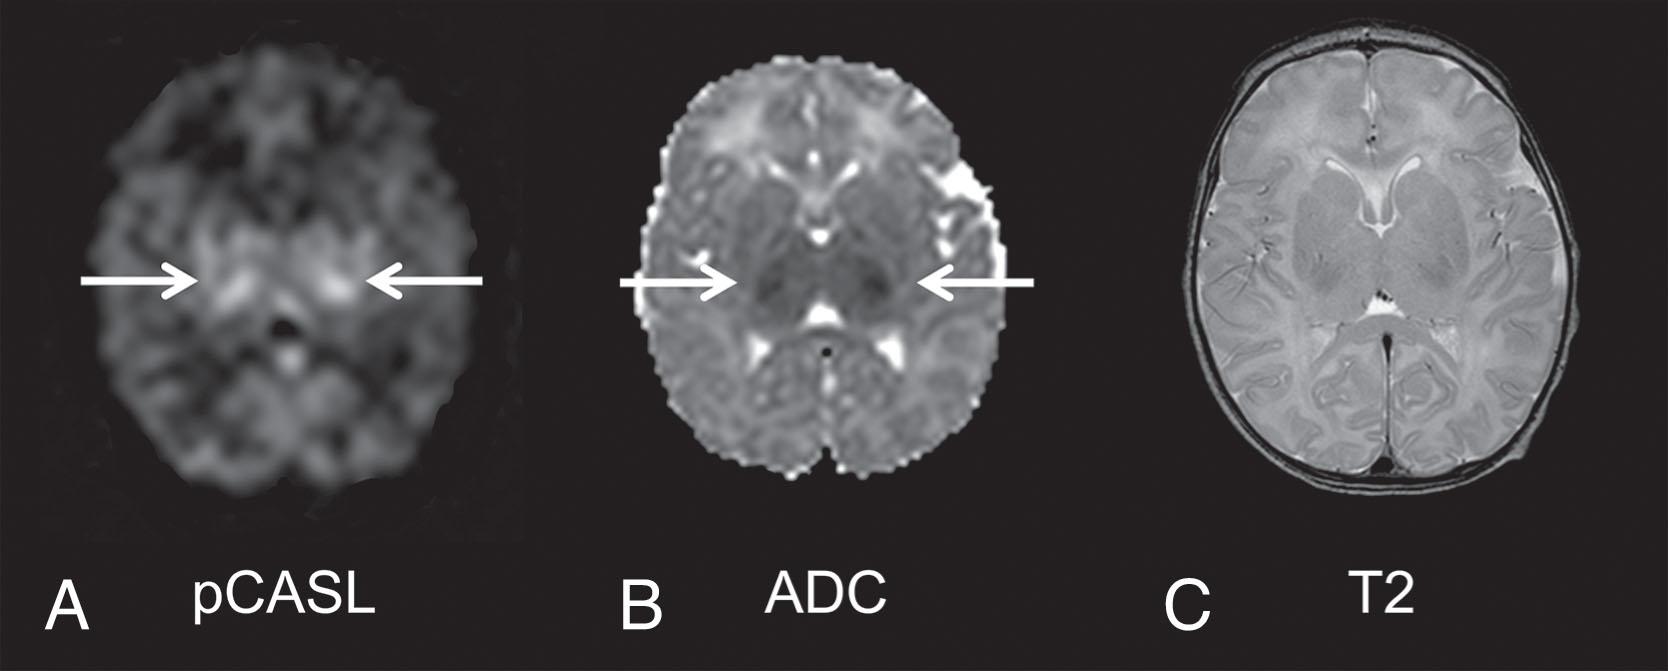

Characteristic pathophysiological changes may be distinguished during this critical latent phase compared with the secondary phase (see Fig. 16.3 ). After restoration of circulation and oxygenation the initial hypoxia-induced impairments of cerebral oxidative metabolism, cytotoxic edema, and accumulation of excitatory amino acids resolve over approximately 30 to 60 minutes. Despite normalization of oxidative cerebral energy metabolism and mitochondrial activity, mean electroencephalogram (EEG) activity remains depressed, and CBF initially recovers, followed by a transient secondary fall. During the subsequent secondary deterioration, starting many hours later (typically approximately 6 to 15 hours after moderate to severe hypoxia-ischemia), delayed seizures develop and then continue for several days, accompanied by secondary cytotoxic edema (cell swelling), accumulation of excitotoxins, failure of cerebral mitochondrial activity, with hyperemia (“luxury perfusion” in excess of tissue requirements; a clinical example is shown in Fig. 16.9 ) and, ultimately, cell death. In contrast, secondary edema and seizures are not seen after milder insults that do not cause cortical necrosis.

Fig. 16.9, An asphyxiated newborn treated with hypothermia showing basal ganglia injury on magnetic resonance imaging (MRI) obtained on day 2 of life. (A), Cerebral blood flow map obtained by pseudocontinuous arterial spin labeling (pCASL) , showing higher perfusion (arrows) in the bilateral thalami and, to a lesser extent, in the bilateral posterior limb of internal capsule and lentiform nuclei. (B) Apparent diffusion coefficient map showing restricted diffusion (arrows) within the same areas. (C) Axial T2-weighted image; changes of T2-weighted images are subtle.